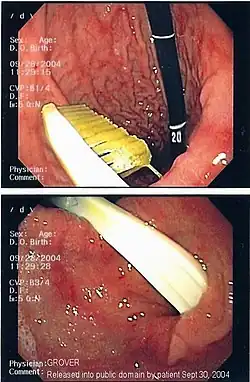

-

A coin seen on AP CXR in the esophagus -

A coin seen on lateral CXR in the esophagus -

AP X ray showing a 9mm battery in the intestines -

Lateral X ray showing a 9mm battery in the intestines -

Multiple button batteries in the stomach -

Button battery in the stomach